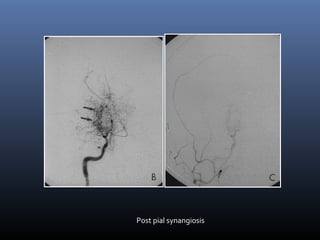

Moya- Moya disease- Imaging

Pial synangiosis- Dilated superficial

temporal and middle meningeal arteries

 Infarctions-

 Intense enhancementof basal ganglia

 Enhancement of dilated deep medullary veins in

centrum semiovale

 Pial collateral enhancement

 DSA- Puff of smoke appearance

Post pial synangiosis